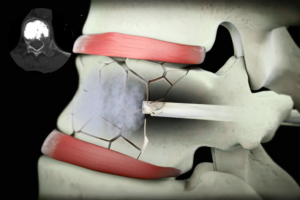

Vidasız kanal daralması ameliyatı, omurga kanal daralması tanısı olan ve omurlar arasında hareketli bir kayma (instabilite) saptanmayan hastalarda uygulanan, özellikle ileri yaşta ve ek hastalıkları bulunan bireyler için avantajlı bir cerrahi yöntemdir. Bu hasta grubunda temel hedef, omurgayı vida ve platinlerle sabitlemekten ziyade, sinirler üzerindeki baskıyı ortadan kaldırarak hastanın günlük yaşam kalitesini artırmaktır.

Eğer omurlar arasında kayma yoksa ya da mevcut kayma sabit, ilerleme göstermeyen ve dinamik grafilerde hareket artışı izlenmeyen bir kaymaysa, kanal darlığı yalnızca mikroskop destekli mikrocerrahi dekompresyon ile güvenle tedavi edilebilir.

Bu yöntemde küçük bir kesi ile omurga kanalına ulaşılır; mikroskop yardımıyla sinirlere baskı yapan kalınlaşmış bağ dokuları, kireçlenmiş eklem yapıları ve gerekirse eşlik eden disk dokuları son derece hassas bir şekilde temizlenir. Omurganın taşıyıcı yapıları mümkün olduğunca korunur, bu sayede ameliyat sonrası instabilite riski artırılmaz.

Vertebroplasti ameliyatı, omurga kırıklarında çöken omura özel kemik çimentosu enjekte edilerek ağrının azaltılmasını ve omurun güçlendirilmesini sağlayan minimal invaziv bir tedavi yöntemidir.

Omurga kırığı, travma, düşme veya osteoporoza bağlı olarak omur kemiklerinde meydana gelen ve sinir basısı ile ciddi nörolojik sorunlara yol açabilen önemli bir omurga yaralanmasıdır.